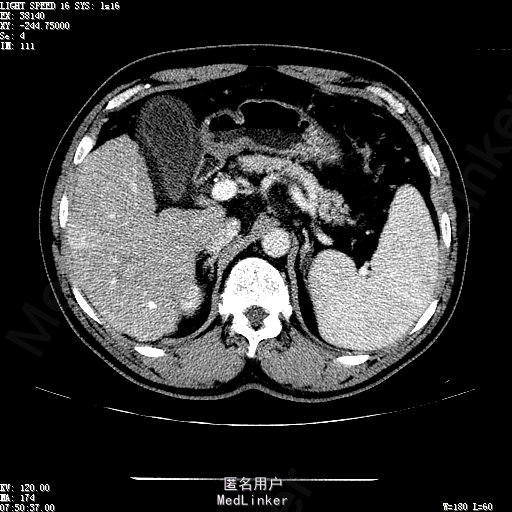

主诉:肝癌TACE治疗后36天 病史:患者两年前体检发现丙型肝炎病毒标志物阳性,于当地医院就诊诊断为"丙肝肝硬化",口服药物治疗,具体用药不详。定期复查肝功及肝脏影像学检查,2月前于医大二院行肝脏增强磁共振检查发现肝S6段动脉期增强结节,36天前在我院行DSA肝动脉造影明确"原发性肝癌"诊断并行"TACE"治疗,术后恢复良好,现患者为进一步行肝癌局部消融治疗来诊。

诊断:1、丙肝肝硬化 代偿期;2、原发性肝癌 S5段、S6段 该患诊断明确,既往曾行TACE治疗肝癌,S5段、S6段近右肾上极2处碘油沉积明确,S5段者较大,约2.31cm。超声显示清晰,为防止癌灶复发,适合行射频消融治疗。